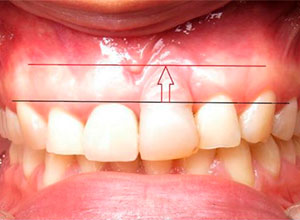

Paciente femenino a la cual le colocaron implante alto verticalmente, presentando a la vista una corona con un excedente de aproximadamente 5 milímetros, de porcelana rosa.

La paciente inconforme con los resultados nos visita, realizamos estudios radiográficos y tomográficos, encontrando que se perdió hueso verticalmente en el implante.